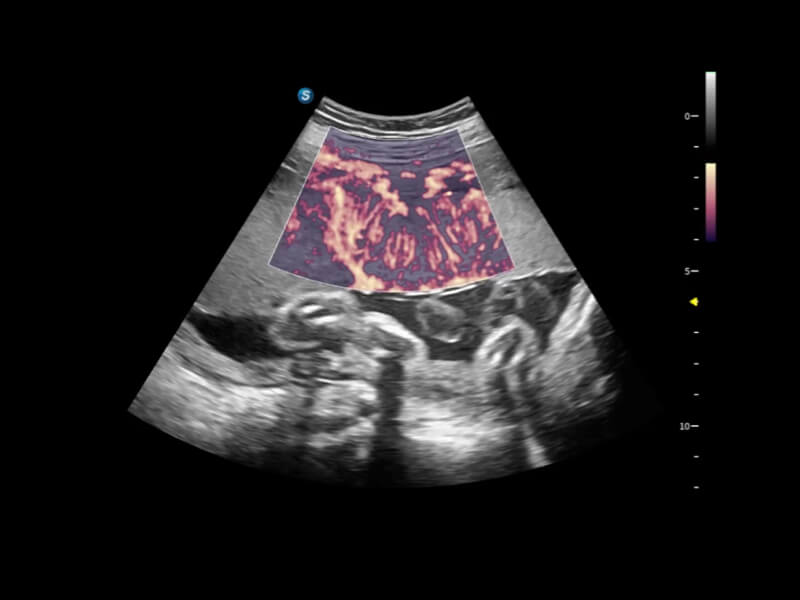

丰富的血流动力学检测技术,可在不同医疗场景中高效捕捉血流信号,助力临床诊疗。

在传统血流的基础上优化扫查和算法策略,能够更好的抑制组织信息,提炼红细胞运动信息,得到更高帧频,高灵敏度和分辨率的血流信号,还原更真实的血流动力学。

通过光照模型,使二维血流显示出立体的效果,增加血流的敏感性、成束性,减少外溢。可以和其他不同的血流技术联合使用,融合不同技术的优势。轻松应对微小血管,增强血流的立体效果,提升视觉敏感性。

通过创新的Matrix E自适应滤波算法,能有效滤除软组织和噪声信号,最大限度保留超低速微细血流的信号;结合超长时间域算法,极大提升细微血流的敏感性和空间分辨率,更真实的反应组织、包块的血流灌注情况。